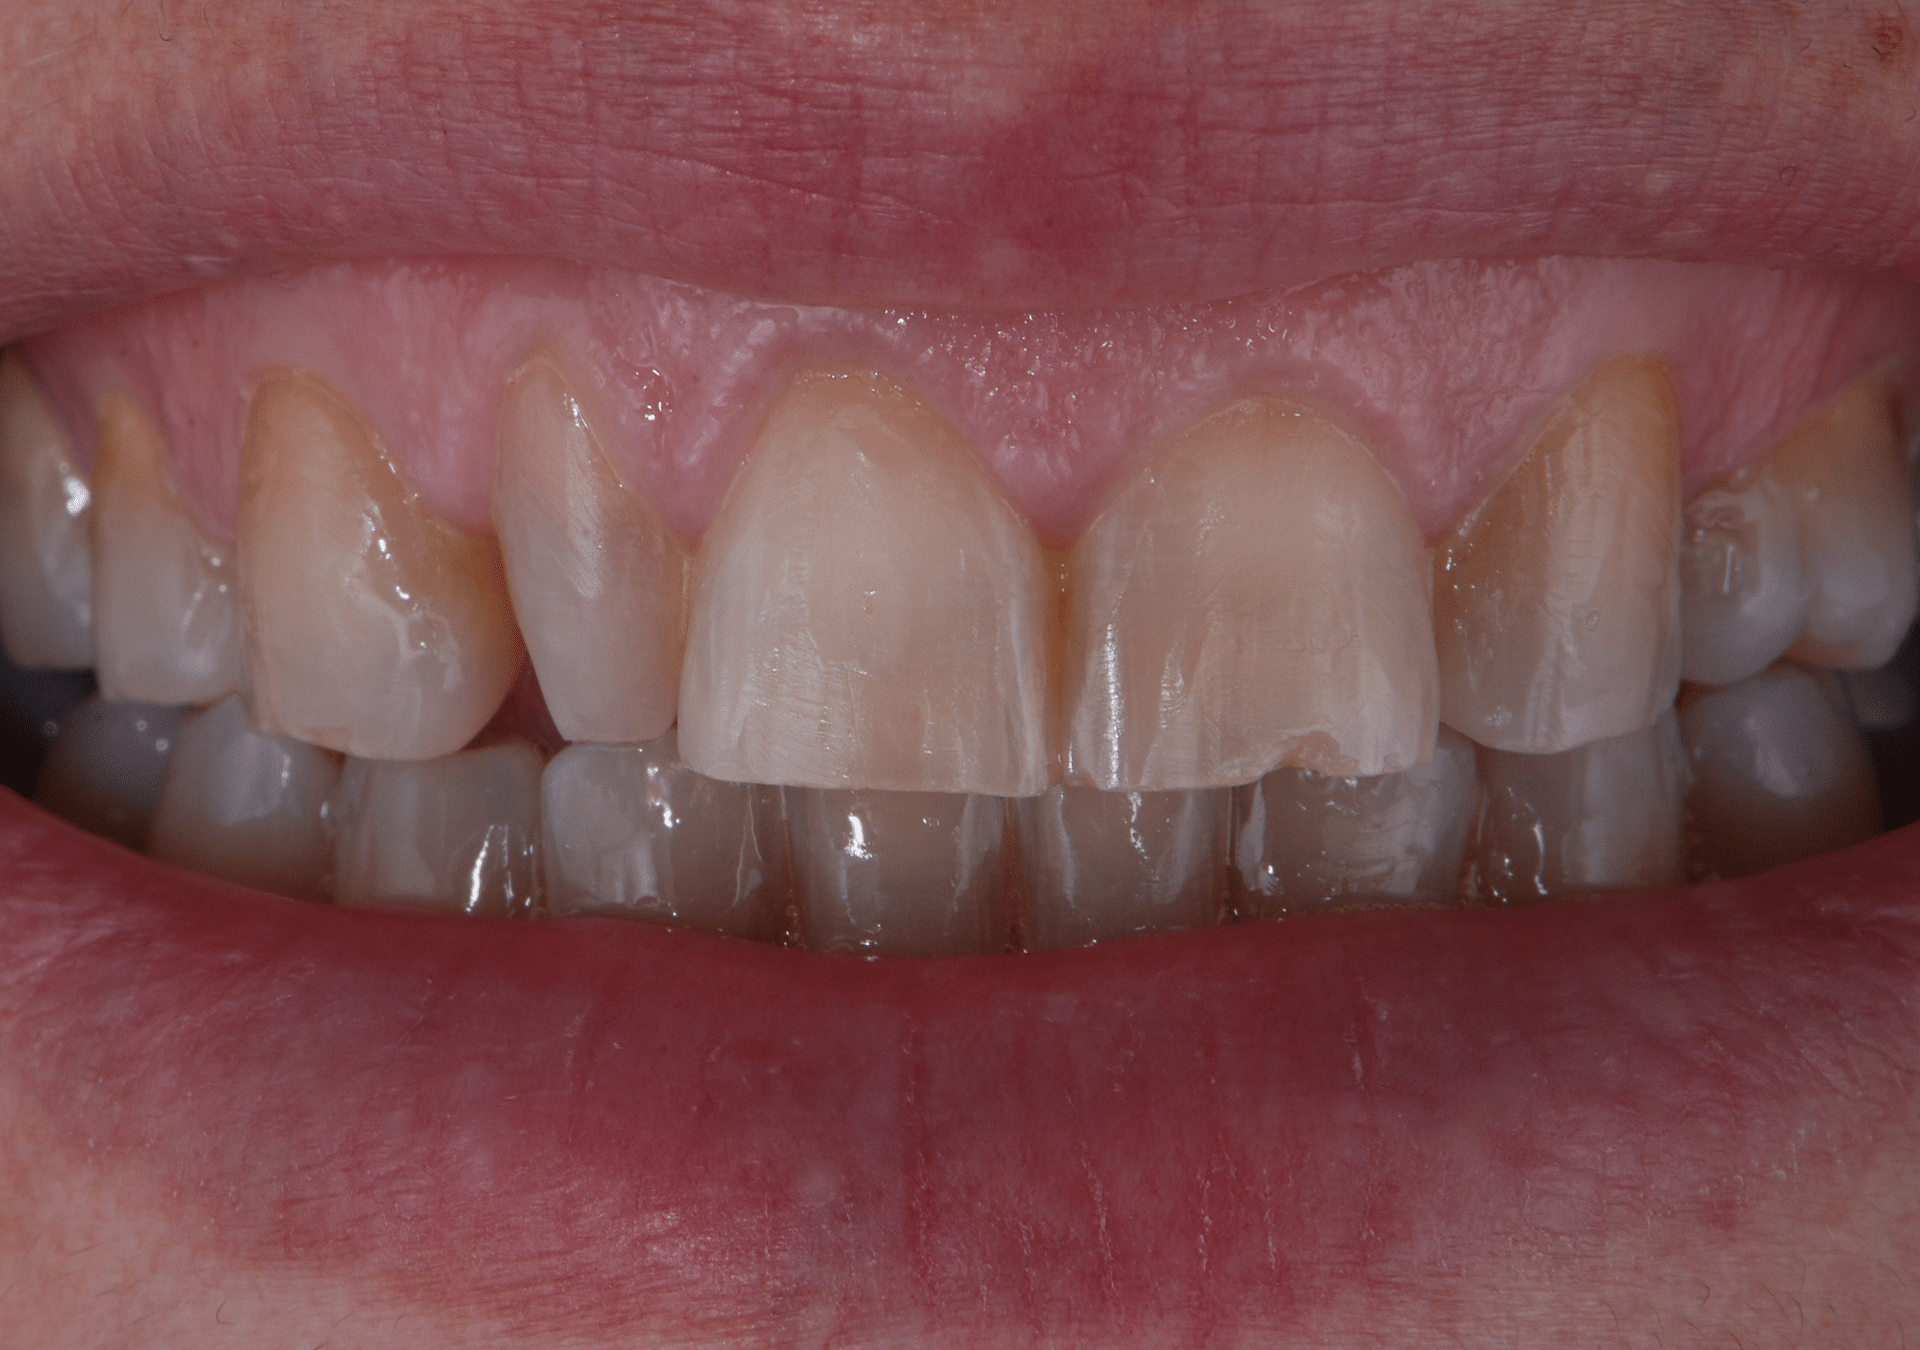

Caso 3

Rehabilitación con cerámica feldespática de dientes con tinción por tetraciclinas y malposición.